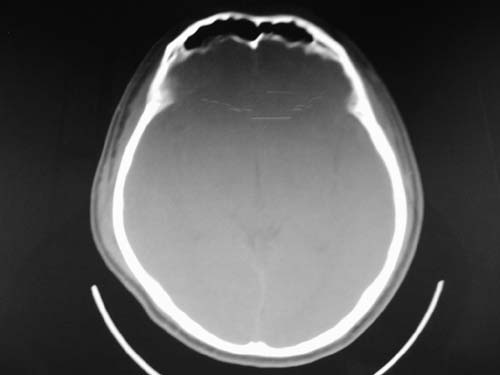

脑中线内血肿,是硬膜下的吗?

脑中线内血肿——硬膜下血肿。

脑中线内血肿——硬膜下血肿。我们一般认为中线即可是硬膜下,也可是蛛网膜下腔的。边缘锐利,张力高的考虑硬膜下的,边缘模糊的,考虑下腔的。如果有老师有肯定的答案,麻烦下给我发个短信

硬膜下血肿,有颅骨骨折

支持镰旁硬膜下血肿,颅骨骨折,头皮损伤.

这个病人年龄不小吧,右侧脑沟不清,中线结构稍有左移,右侧额颞顶及右镰旁硬膜下血肿,另有蛛血,骨折。

外伤后引起的颅骨骨折、硬膜下血肿、皮下血肿,颅骨骨折引起的矢状窦破裂,形成大脑纵裂内血肿。